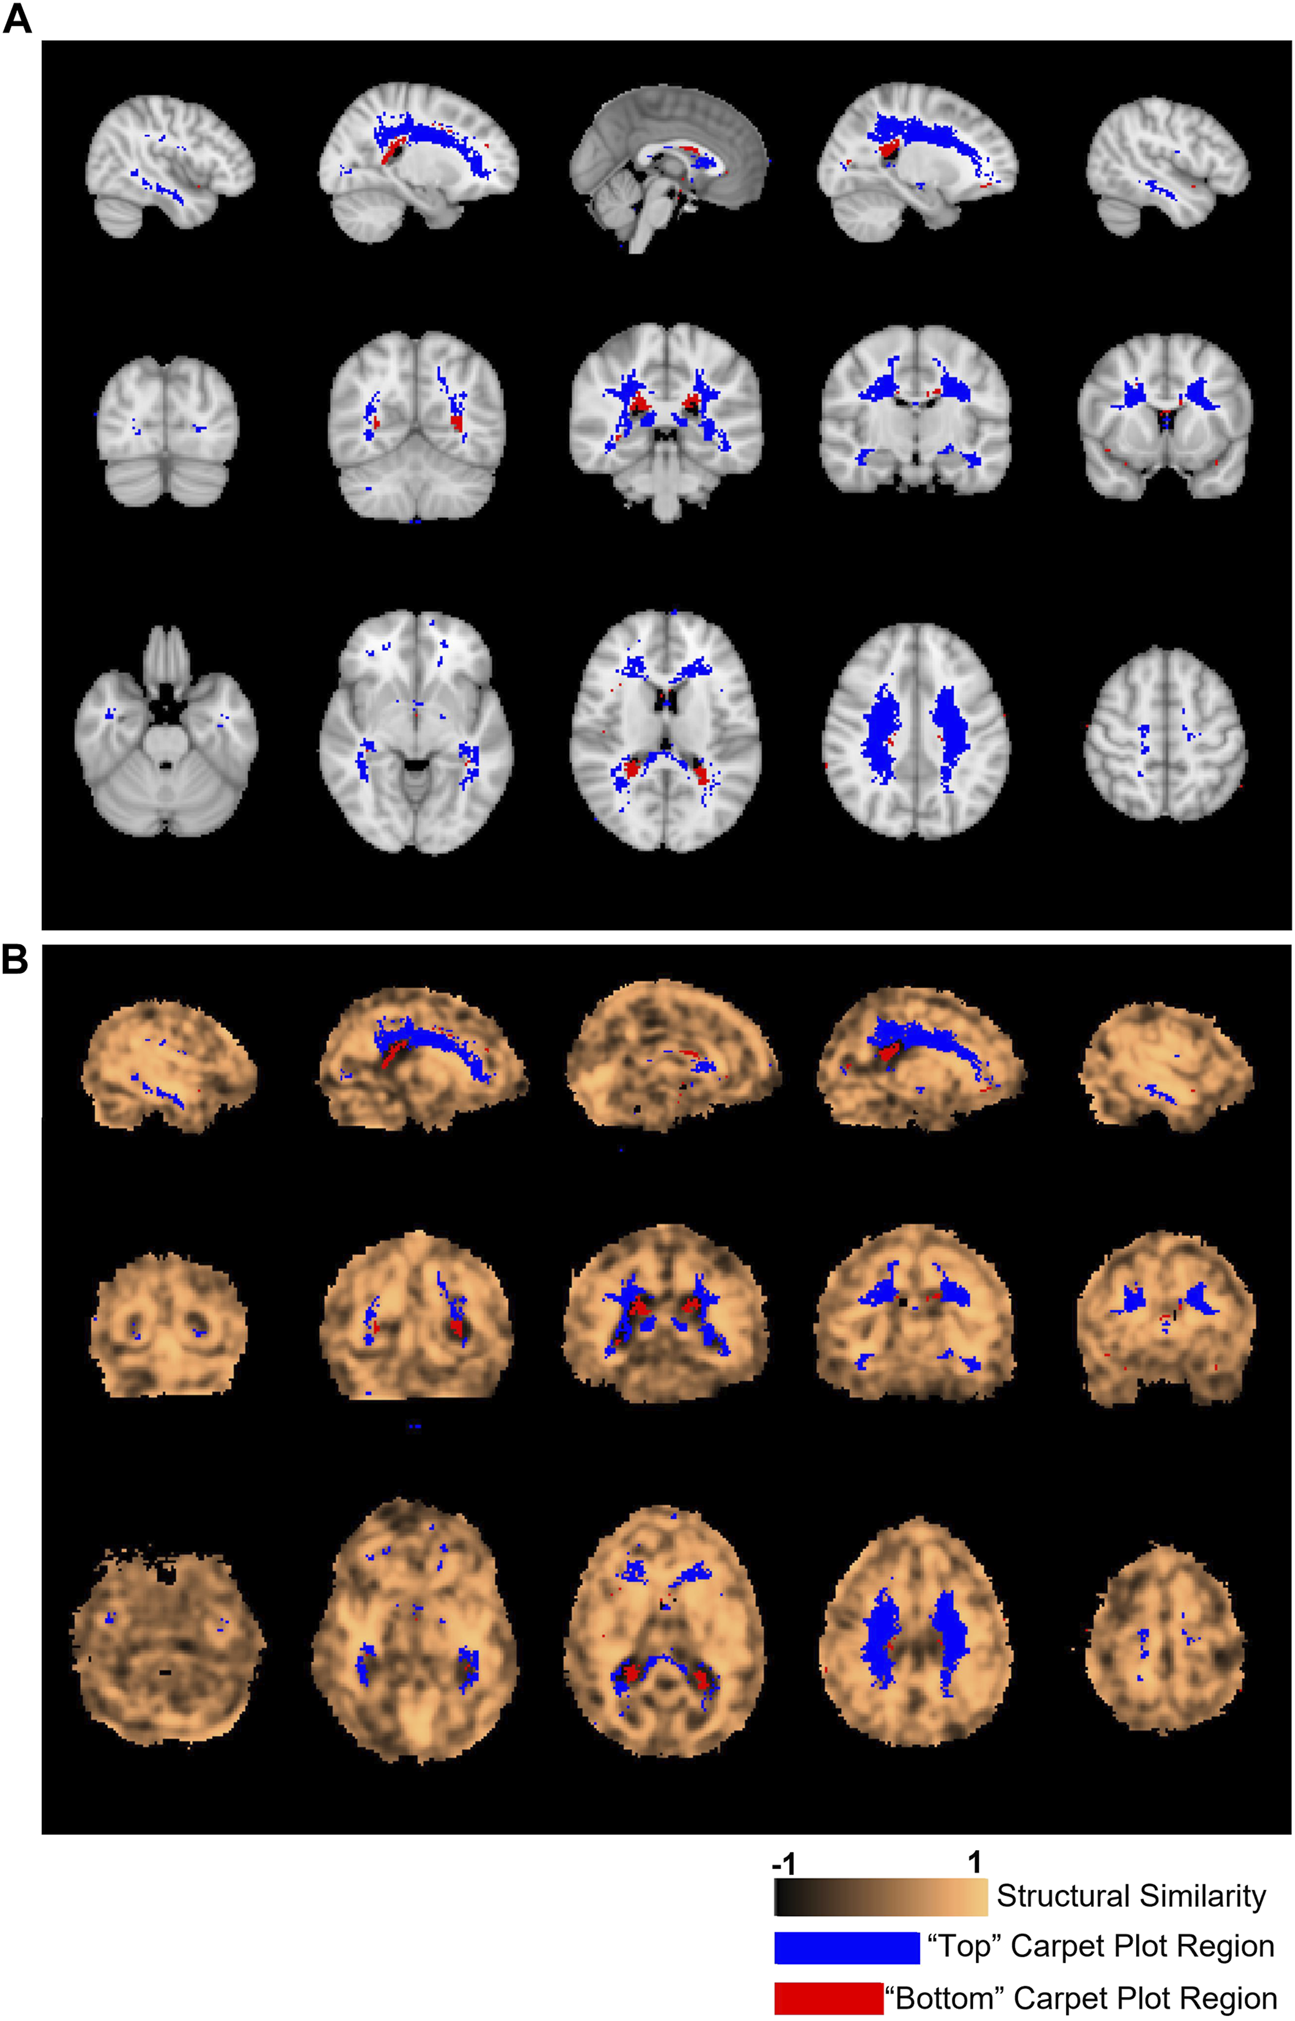

Structural similarity values were averaged over GM regions and over WM regions, with these regions illustrated in Figure 5. In addition, structural similarity values were averaged over the previously detailed carpet plot section masks, which isolate the voxels which commonly belong to the top, middle, and bottom carpet plot regions. A comparison of the top and bottom carpet plot region masks with the computed structural similarity map is shown in Figure 6.

FIGURE 6. Locations of voxels located in top and bottom carpet plot regions and correspondence with structural similarity map. (A) Colored voxels indicate locations corresponding to voxels which were located in the top and bottom regions of CO2 carpet plots in at least half of all subjects. Blue voxels correspond to those cropped from the top of the carpet plot (with extra long CO2-derived delay times), while red voxels correspond to those cropped from the bottom of the carpet plot (with extra short CO2-derived delay times). (B) The same cropped carpet plot voxels from (A) are overlaid on the structural similarity value map comparing the subject-averaged DSC-TTP delay map with the subject-averaged CO2-arrival delay map.

Figure 6A displays the location of the top and bottom carpet plot region masks, which represent areas of the brain that were assigned to either the top or bottom carpet plot regions in at least half of subjects. These same voxel masks are overlaid in Figure 6B with the structural similarity map comparing the subject-averaged CO2 delay map with the subject-averaged DSC delay map. The average structural similarity

One of the primary issues of the maximum cross-correlation method applied to CO2-MRI is the resulting wide spread of CO2-derived delay values. To better understand this spread, we analyzed which voxel locations corresponded to those cropped from the top of CO2 carpet plots (indicating extra long CO2-derived delay values) and voxel locations which corresponded to those cropped from the bottom of CO2 carpet plots (indicating extra short CO2-derived delay times). These voxel locations are displayed in Figure 6. Observation of these voxel locations reveals that voxels with extra long CO2-derived delay times were primarily located in areas of deep WM in the brain. This also explains the observation that these voxels have lower signal-to-noise ratio compared with those in the middle carpet plot portion. This pattern of longer delays and lower signal-to-noise ratio in areas of deep WM is consistent with the results observed in the DSC-MRI data and in previous papers (Thomas et al., 2013b; Bhogal et al., 2015; Poublanc et al., 2015; Bhogal, 2021; Poublanc et al., 2021). Further, the observed BOLD signal pattern in each voxel is impacted by both the arrival of CO2 to the voxel and the blood vessel dilation which occurs due to CO2 being a vasodilator. Some studies (Bhogal et al., 2015; Niftrik et al., 2017) suggest that cerebrovascular reactivity, a measure of the magnitude of the response of brain regions to the effects of CO2 arrival, tends to be lower in regions of deep WM, which could suggest that the extra long CO2-derived delays observed in these regions in CO2 delay maps could also be influenced by low cerebrovascular reactivity in those areas. Additionally, results from Bhogal (2021) confirmed that reactivity in WM is notably different than that of GM and showed that the response of WM is also influenced by venous draining topology. Despite these sources of potential confounding of the assigned delay time within these voxels, analysis of the structural similarity map within the brain region mask associated with the top of the carpet plots (see Figure 6B) revealed that these voxels had equal, possible higher, structural similarity compared with those from the middle of the carpet plots. This suggests that these voxels with very long CO2-derived delays have similar reliability in their ordering with those from the middle of the carpet plot (whose delay times are expected to be more reliable) in terms of structural similarity to the DSC delay map.

4.4.2 Bottom of carpet plot

Voxels which were removed from the bottom of the carpet plot were primarily located in regions near the boundary between WM and the lateral ventricles, particularly toward the posterior side of the brain. These voxels correspond to locations where the computed delay value was more than 10 s earlier than the average CO2-derived delay time across the brain, which likely cannot reflect true arrival of the CO2 given that the increased arterial CO2 would not likely occur so early in these specific voxels. We also note that these voxels at the bottom of the carpet plot were more likely to have BOLD time series which were negatively correlated with the global average time series. Analysis of the correlation values obtained during the cross-correlation delay computations revealed that voxels with negative correlations appeared in the bottom, middle, and top carpet plot regions at rates of 35%, 2%, and 21% on average, respectively.

Such observations (namely, of negatively correlated BOLD signals near the edge of the ventricles and with signal changes earlier than most voxels across the brain) align with previous studies (Bianciardi et al., 2011; Thomas et al., 2013a; Bright et al., 2014) which suggest that negative BOLD signal correlations are predominantly due to blood volume change instead of cerebral blood flow (CBF) increase. This volume change is due to dilation of ventricular vessels accompanied by shrinkage of cerebrospinal fluid (CSF) space, resulting in signal decrease which could overpower any BOLD signal increase. This hypothesis also explains the very short CO2-derived delays calculated for voxels with negatively correlated BOLD signals since CSF shrinkage could occur prior to the arrival of the CO2. Alternatively, another mechanism which could cause negatively correlated BOLD signals is the cerebral “steal effect”, in which multiple CBF changes (both increased and decreased CBF response in regions in and surrounding the voxel) simultaneously occur in response to the arrival of the CO2, meaning that regions with reduced CBF are compromised due to the increased CBF in other regions (Brawley, 1968; Poublanc et al., 2013; Sobczyk et al., 2014). Finally, one might hypothesize that the Bohr effect (Riggs, 1988), under which increased concentration of CO2 in the blood causes a decreased oxygen binding affinity in hemoglobin (thus increasing concentrations of deoxyhemoglobin), could theoretically cause a BOLD signal decrease in response to elevated blood CO2. However, the magnitude of any such signal changes due to the Bohr effect is expected to be very small. This claim is supported by the fact that an increase of 10 mmHg from baseline in end-tidal CO2 should only cause a very small shift in the oxyhemoglobin dissociation curve for normal blood partial pressure of O2 (PO2) (Levitzky, 2013), where normal arterial PO2 typically falls within the range of 75–100 mmHg (Ortiz-Prado et al., 2019). Further investigation is still needed to definitively explain this phenomenon of certain voxels displaying decreased BOLD signal in response to the CO2 bolus. As demonstrated in Figure 6B, the voxels with very short CO2-derived delay values corresponded with areas of the SSIM value map which were particularly low, indicating that these unrealistically low delay times are likely one of the main factors which differentiates the CO2 delay maps from the DSC delay maps.